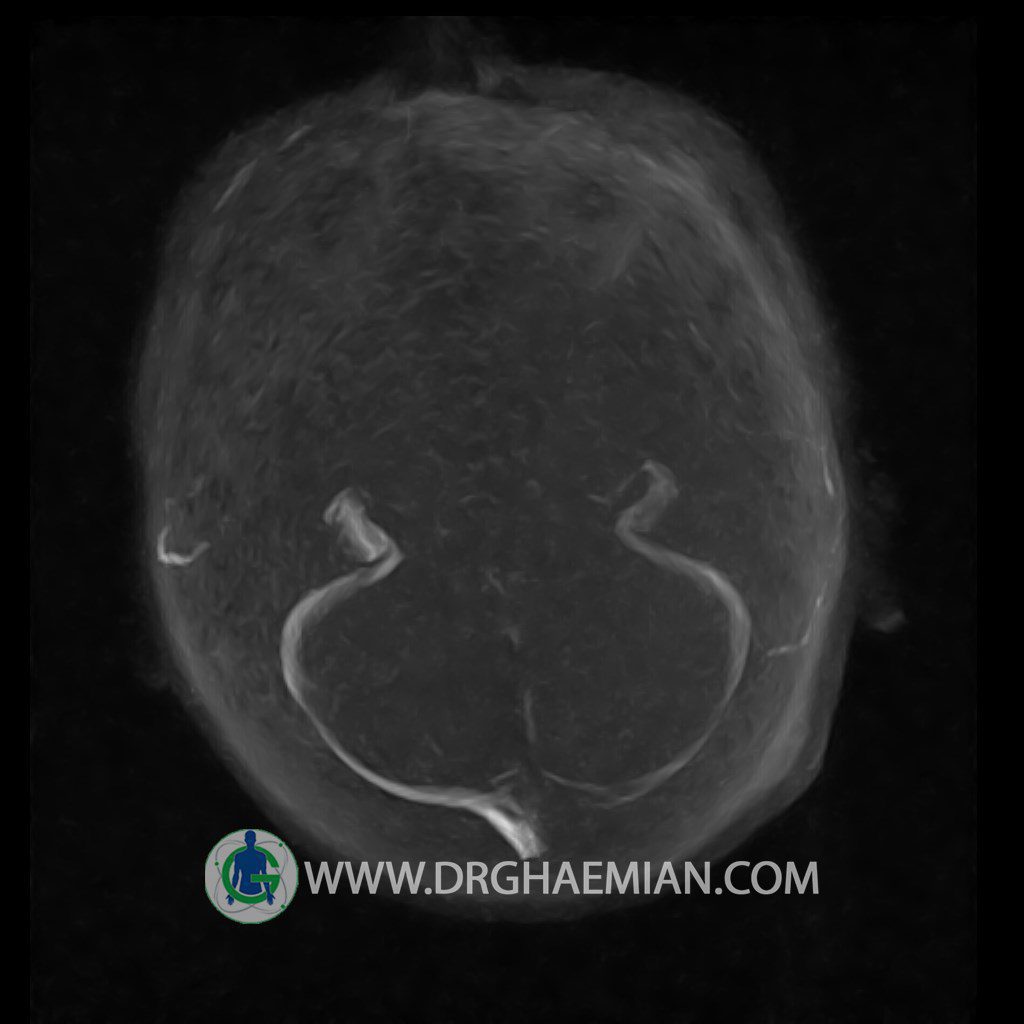

CRANIAL MRV

Technique: TOF ( time of flight ).

Images of the venous cranial vessels demonstrates a superior sagittal sinus of normal caliber with normal arrangement of draining superficial cerebral veins.

The great cerebral vein Galen inferior sagittal , straight sinus and left sigmoid sinuses appear normal.

The right transverse and sigmoid sinuses present a normal caliber.

– Narrowing of left transverse sinus without inthimal irregularity & without filling defect suggestive for cengenital hypoplasia